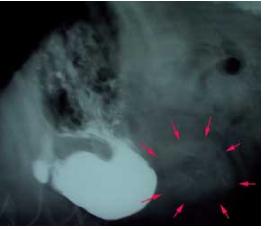

Xrays were taken of the stomach and intestines and they indicated a possible foreign body in the small intestine. Barium was given to the dog, but this failed to move through the small intestines confirming that the dog was totally blocked.

The dog went to surgery to remove the unusual item in the intestines.